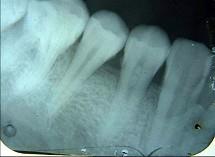

以下哪一项是诊断牙髓钙化的主要手段 ( )

- A.电活力测验

- B.视诊

- C.X线片检查

- D.温度测验

- E.光纤透照

C